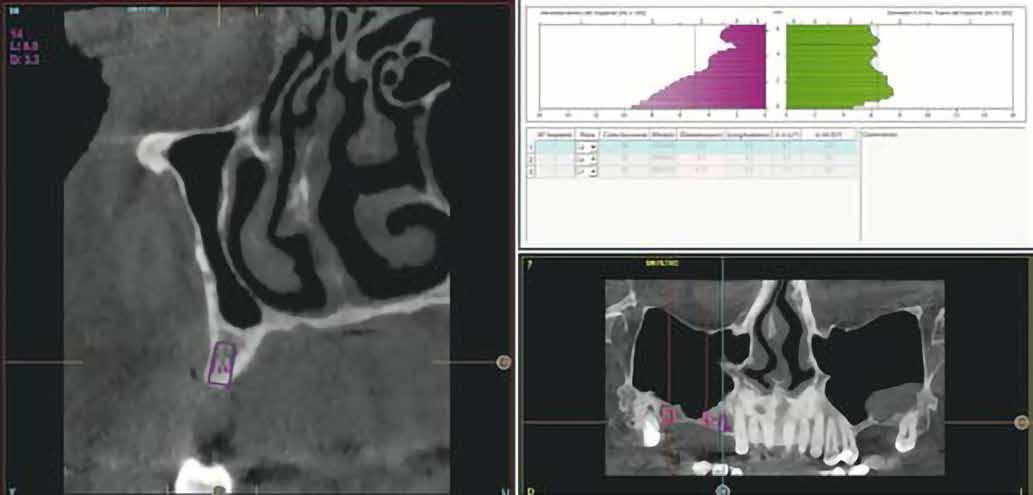

A-PRF membránokkal borítottuk (7. ábra). A mukogingivális lebenyt – annak megnyújtása nélkül – a helyére fektettük és varratokkal rögzítettük, per primam sebzárást nem végeztünk (8., 9. ábra). A varratokat 2 hét után távolítottuk el, a varratszedésig a sebgyógyulás támogatására per os 1000 mg/nap C- és 12 000 NE/nap D-vitamint adtunk (20). A műtéti beavatkozást 24 hét gyógyulási időszak követte, melynek során sem helyi, sem gyógyszeres kezelés nem történt, az esztétikum javítása érdekében a páciens ideiglenes kivehető fogpótlást használt. A csontos gyógyulás ellenőrzése és az implantáció tervezése céljából állcsonti CT felvételt készítettünk, illetve lenyomatvételt végeztünk. A CT felvételen tökéletes csontos gyógyulást észleltünk, az alveolaris csont volumene teljes mértékben megtartott volt (10. ábra), a klinikai kép is ennek megfelelően alakult (11., 12. ábra)

A Trishape Implant Studio™ a korábbi csont augmentáció területén, a felső állcsontnál áltagosnak számító D2-D3 csontminőséget jelzett (13. ábra). A lenyomat alapján készített gipszmodellt szkennelve virtuális mintát nyertünk. A CBCT felvétel és a virtuális modell adatait a Dual Scan protokoll (21) elveinek megfelelően használtuk fel az implantációs sablon (New Age Dental Kft, Nemeskéry Károly) készítéséhez (14., 15., 16. ábra). Az implantátum (Ankylos C/X A11) behelyezése teljesen navigált módon, 35 Ncm primer stabilitással történt (17., 18. ábra). Az implantátumra a fogtechnikus (D1 Dental Kft., Garamvári Csaba) által előzetesen

és jelentős mobilitással rendelkezett. A radiológiai vizsgálat után egyértelműen látszódott, hogy a fogon még nem végeztek gyökérkezelést. A 2.6-os és 2.7-es fogaknak megfelelő területen az arcüreg kiterjedése jelentős volt, vertikális csontmennyiség szignifikánsan csökkent (1. és 2. ábra).

A 2.6-os fog helyén egy 6 mm mély furatot készítettünk a gyártó előírása szerint, a puha csont protokoll lépéseit követve. Egy ∅ 5.0 mm × 6 mm Straumann® BLX implantátumot helyeztünk be 50 Ncm-es behajtási nyomatékkal (5. ábra)

A 2.7-es fog helyénél egy disztális irányú, 14 mm mély, ferde előfúrást végeztünk, elkerülve a sinus maxillarist a tuber csontkínálatának felhasználásával. Egy ∅ 5.0 mm x 14 mm Straumann® BLX implantátumot helyeztünk be, 50 Ncm-es behajtási nyomatékkal (6. ábra)

Hathetes gyógyulás után a lágyszövetek kiválóan gyógyultak, és minden implantátum megfelelően osszeointegrálódott, amelyet a radiológiai vizsgálat is megerősítetett (9. és 10. ábra).

A végső röntgenfelvételen láthatjuk az osszeointegrálódott implantátumokat, valamint a stabil kresztális gerincet az azonnal behelyezett, a rövid és a ferde, a tuberben elhorgonyzott implantátum körül (12. ábra).